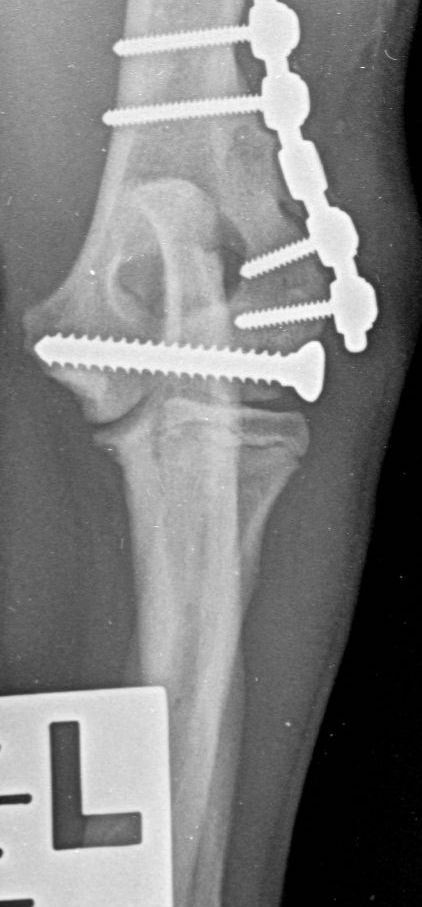

These concerns have led to recommendations being altered over the past decade or so, with veterinarians now using bone plates, instead of K-wires, as an adjunct to a transcondylar screw when managing humeral unicondylar fractures (Figure 2), even in puppies (Figure 3) (Clark, 2016; Kvale et al., 2022). However, the basis on which this conclusion for puppies was reached appears to have been flawed because it assumed that what had been shown to be the case for adults would also apply to immature patients. As the conclusion was felt to conflict with the author’s experience of treating such patients, a retrospective study was undertaken to evaluate complications and outcomes in immature dogs treated for humeral unicondylar fractures at one centre over a 10-year period (Butterworth, 2022). The findings of this study are summarised in this article.